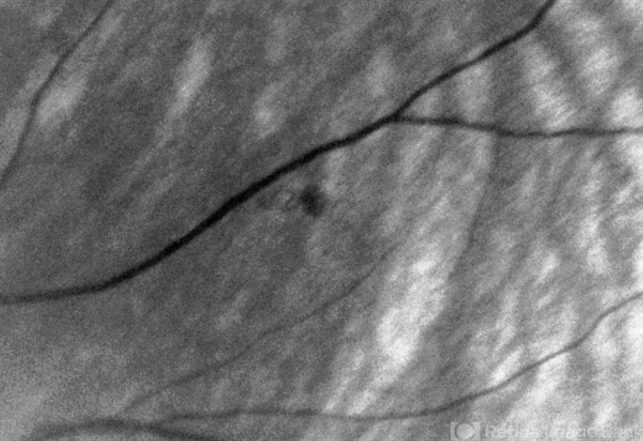

- Unusual presentation of VHL juxtapapillary hemangioblastoma detached from retina with feeder vessels

- Von Hippel-Lindau, retinal hemangioblastoma

Red Free - Description

- Same pateint, a different lesion: Very small lesion that appeared to be a very early hemangioblastoma, laser performed.